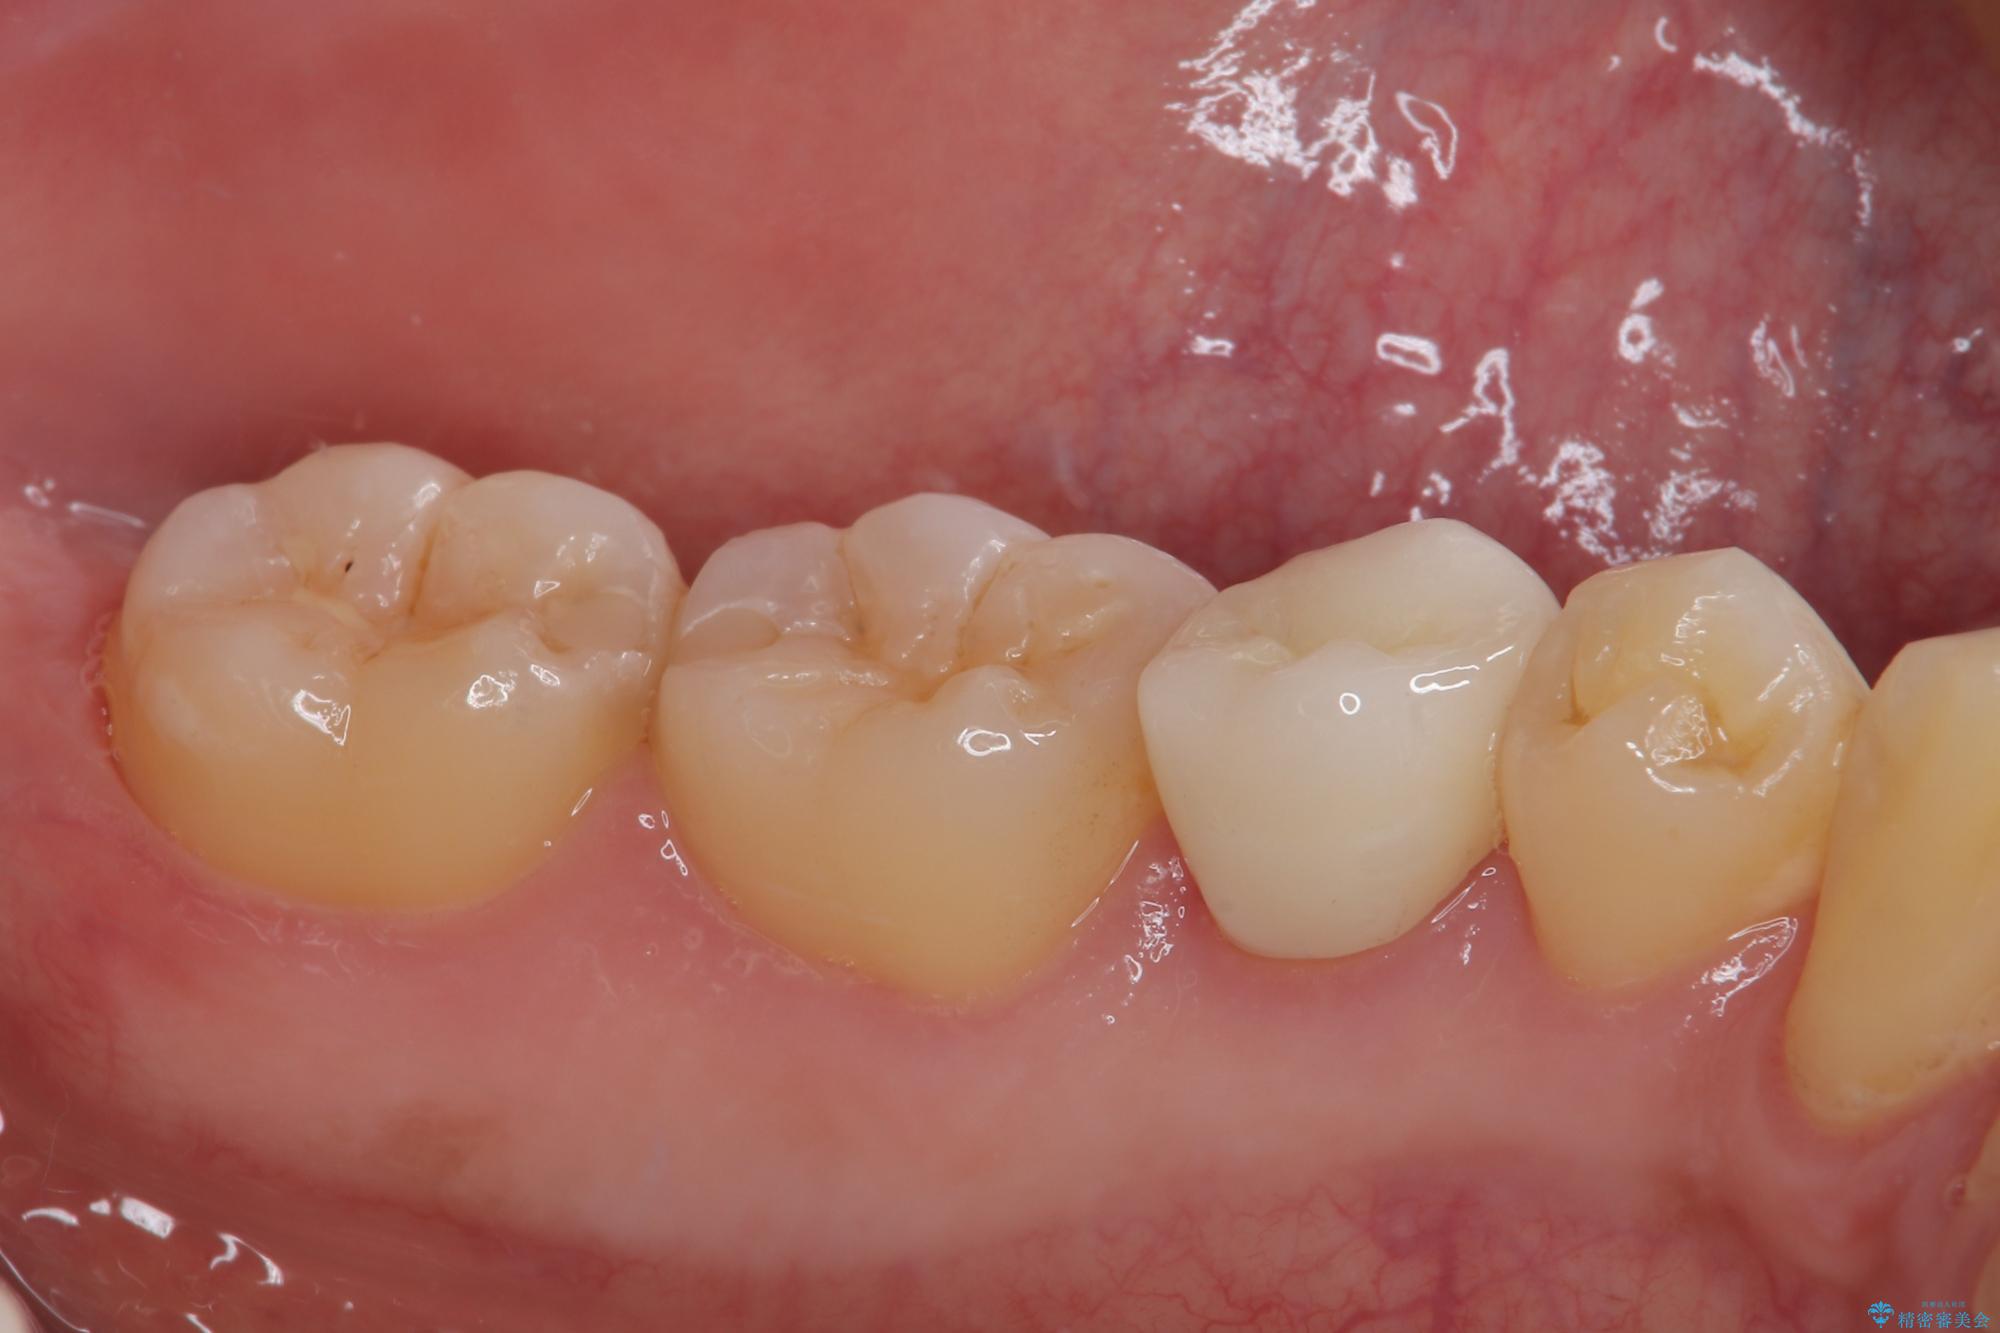

左下にフロスを通すと引っかかる オールセラミッククラウン

- 左下の奥歯のところがフロスが引っかかったり、ちぎれたりするとのことで来院された患者様です。検査の結果、神経は正常な反応を示し、フロスは引っかかる状態でしたので、虫歯治療も併せて行うためにオールセラミッククラウンによる補綴治療を行っていくことにしました。

拡大鏡視野下でプラスチックの詰め物、虫歯を除去しオールセラミッククラウンに適した形に整えました。

歯と歯茎の間に圧排糸と言われる糸を入れてシリコーン印象材にて型どりをしました。

フロスがちぎれることもなくなり、被せものが入っていることを忘れていたと大変喜んでいただきました。適合の良い被せものは二次的な虫歯の再発リスクを低減してくれます。